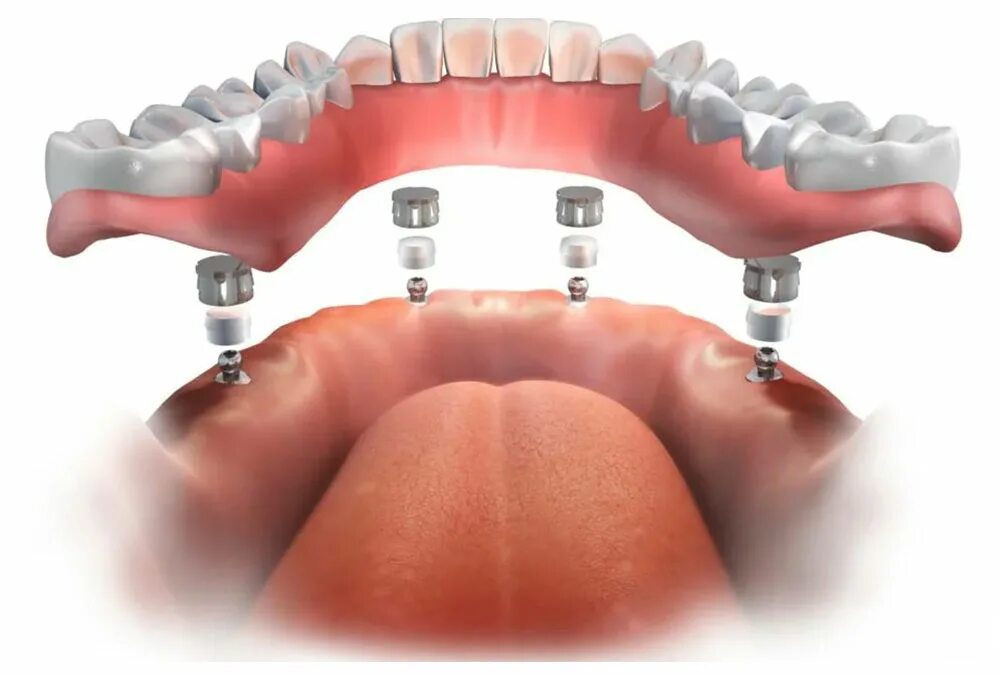

All in установка